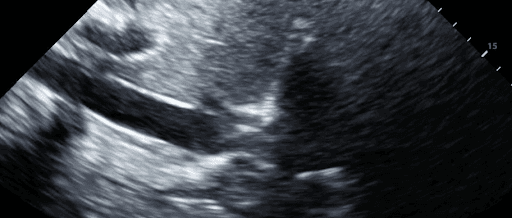

While tension pneumothorax is largely a clinical diagnosis, certain ultrasound features can point to its presence. Notably, a fixed and dilated inferior vena cava (IVC) and the absence of respirophasic variation observed from a subcostal window suggest a pathologically elevated central venous pressure, consistent with obstructive shock. Additionally, a hyperdynamic, underfilled right heart indicates tension physiology.